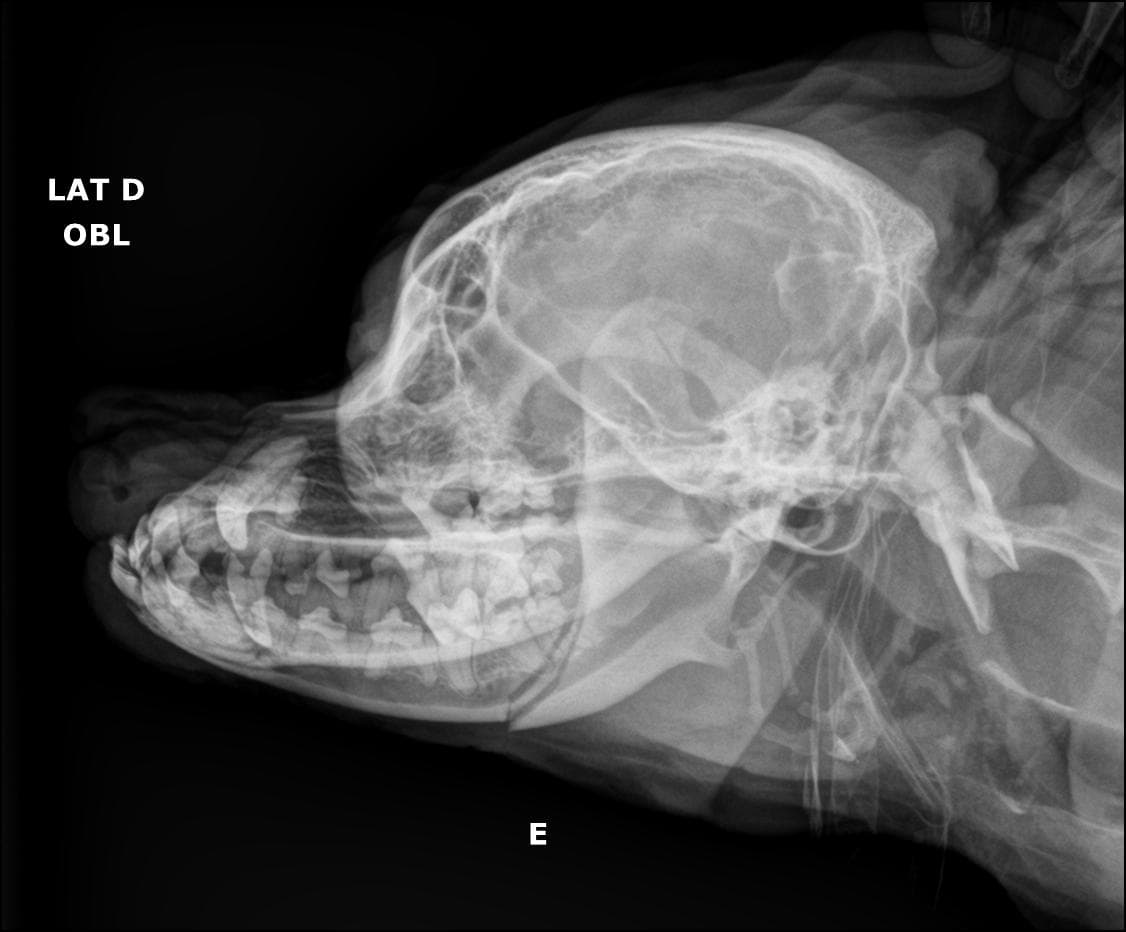

Nosso serviço de radiologia digital é projetado para oferecer diagnósticos precisos para cuidar da saúde dos pets. Contamos com equipamentos de última geração que nos permitem capturar imagens de alta qualidade e definição, fornecendo uma visão clara das estruturas. Essa tecnologia avançada nos permite identificar diversas condições médicas com maior precisão e detalhamento.